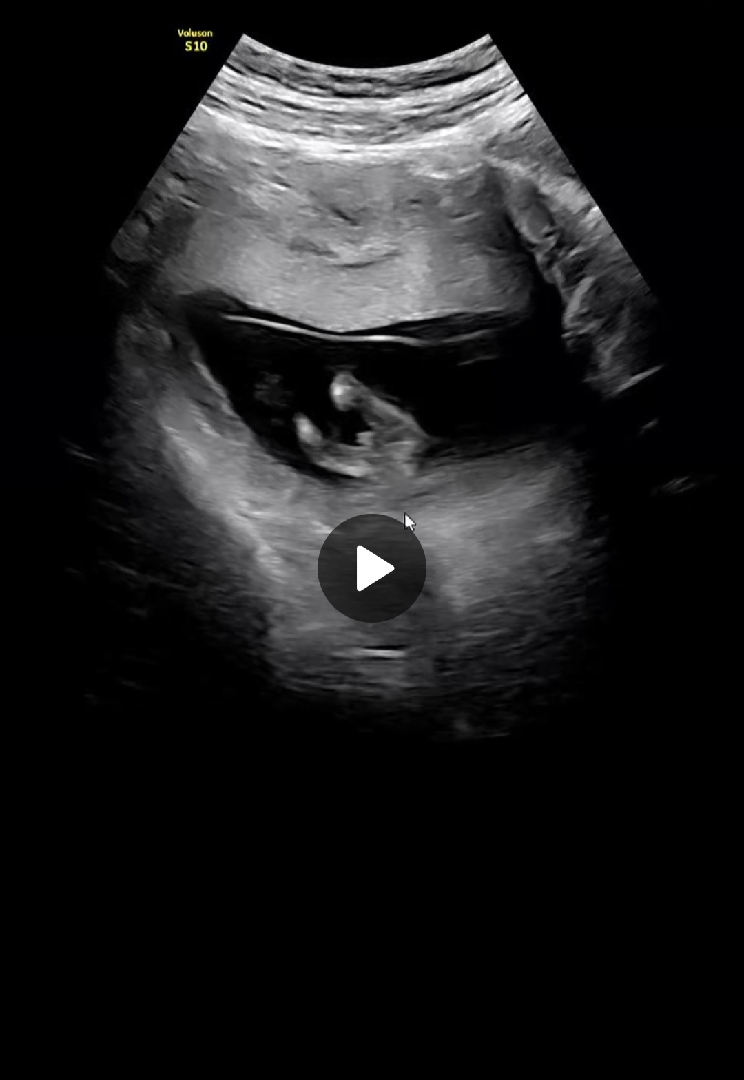

12주 5일차 초음파

다리사이에 보인다고 원장님이 말씀하셨는데 아직 확정하기엔 빨라서 16주때 다시 보면서 말씀드리겠다 하셨는데 아들...맞을까요? 없어지진 않겠죠..??